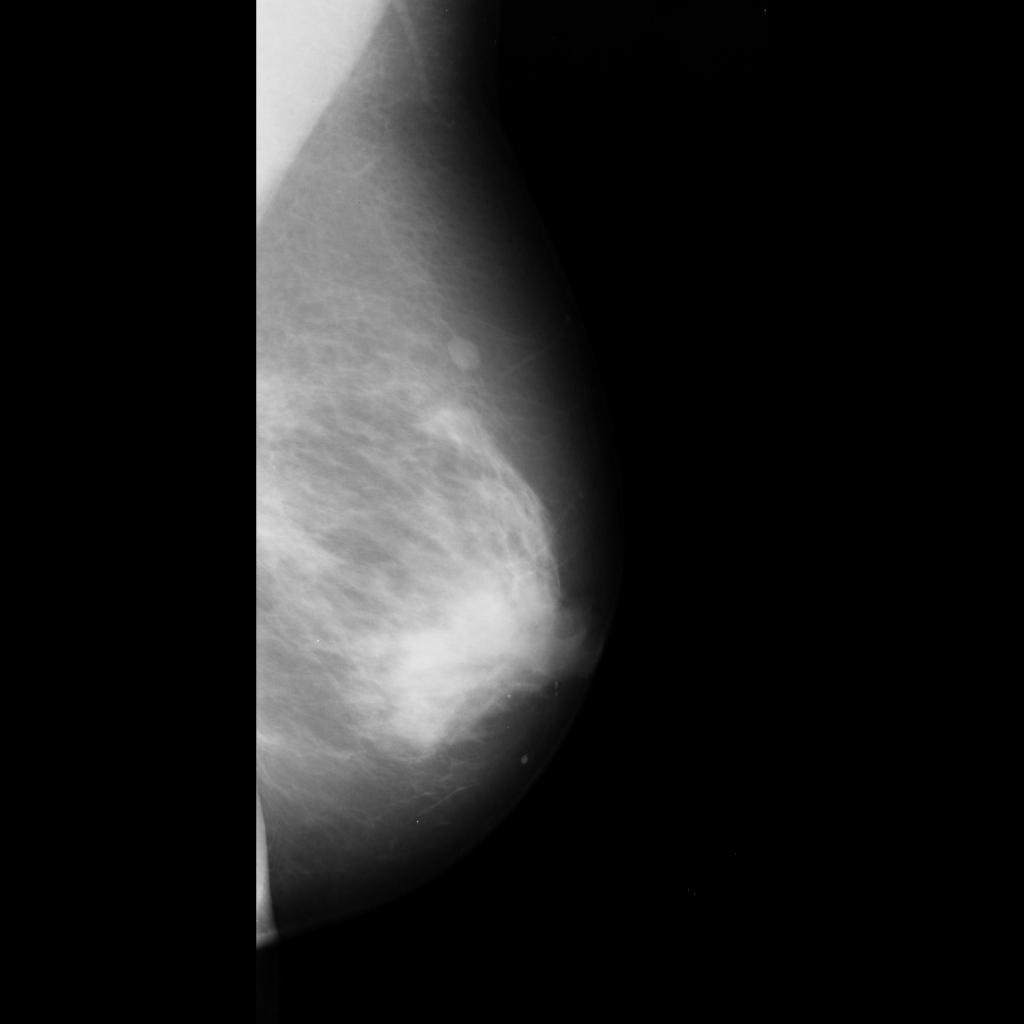

benign

malignant